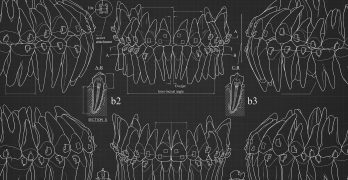

Baja las guías de posicionamiento de brackets del Dr. Tom Pitts

¿Por qué colocan los brackets tan a gingival? ¡Mis ojos no pueden ver eso! ¡Ese bracket esta mal colocado!. De antemano … [Leer más...] acerca de Baja las guías de posicionamiento de brackets del Dr. Tom Pitts